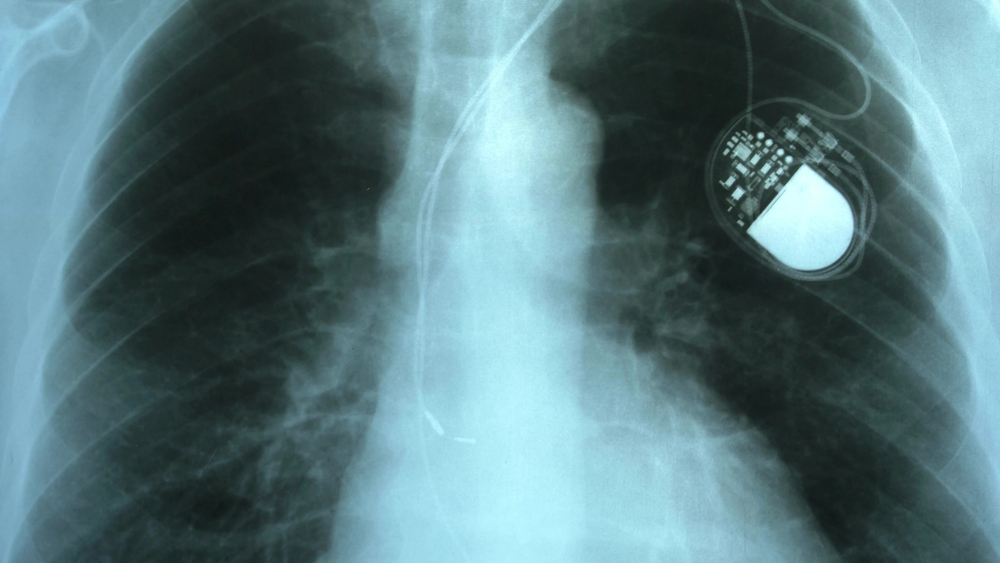

1. The Silent Pacemaker Recall

Pacemakers are supposed to keep hearts steady, not stop them altogether. Yet several times over the past decade, certain models were quietly pulled from shelves due to faulty batteries that could suddenly die. Instead of broad public announcements, the recalls often went only to hospitals and cardiologists, leaving patients completely in the dark. Imagine trusting your life to a heartbeat helper, only to find out it could malfunction without warning. The scariest part? Some people never learned about it until their device failed—turning a hidden recall into a near tragedy.